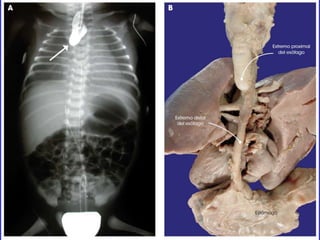

ATRESIA

Oclusión de una abertura natural

ATRESIA Oclusión de unaabertura natural Ej. :Atresia esofágica